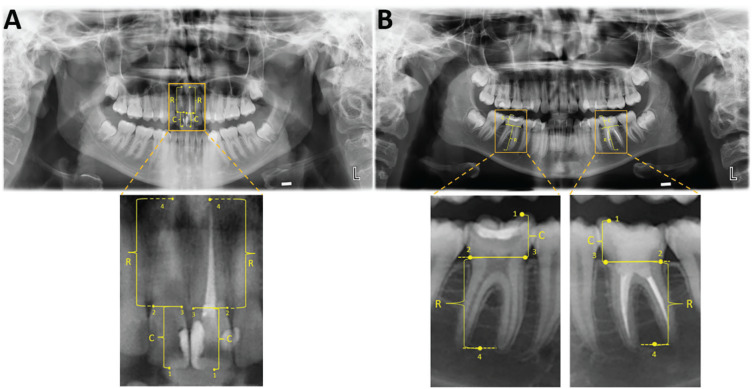

Methods: The study sample included panoramic radiographs of 503 patients (314 females and 189 males; 16.29 years±3.98) with 620 ETT and 580 VPT. The tooth length was measured on digital panoramic radiographs, which were collected at the beginning and end of the orthodontic therapy for each subject. The pre- and post-orthodontic treatment radiographic evaluation included the percentage of EARR in ETT and contralateral VPT for all tooth types. Any relationship between EARR and orthodontic treatment type (one- and two-phase; extraction and non-extraction), duration, and patients' age and gender were investigated. Mann-Whitney U, Wilcoxon signed rank, Kruskal-Wallis and Spearman correlation tests were applied for comparisons and to test the correlations.